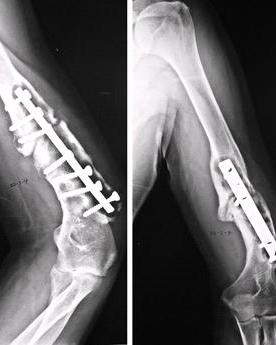

♥肱骨骨折

肱骨骨折常发生于肱骨外科颈、肱骨干、肱骨髁上、肱骨髁间、肱骨外髁、肱骨内上髁。其中,尤以前三者为多,可发生于任何年龄,多由直接暴力和间接暴力所引起,如重物撞、挤压、打击及扑倒时,手或肘部着地,暴力经前臂或肘部传至各部位。X线检查可明确诊断,并提示骨折的类型。中医将肱骨骨折归入“伤骨”范畴,认为本病因多外伤引起脉络受损,气血凝滞,营血离经,阻塞经络而致。中医将肱骨骨折归入“伤骨”范畴,认为本病因多外伤引起脉络受损,气血凝滞,营血离经,阻塞经络而致。